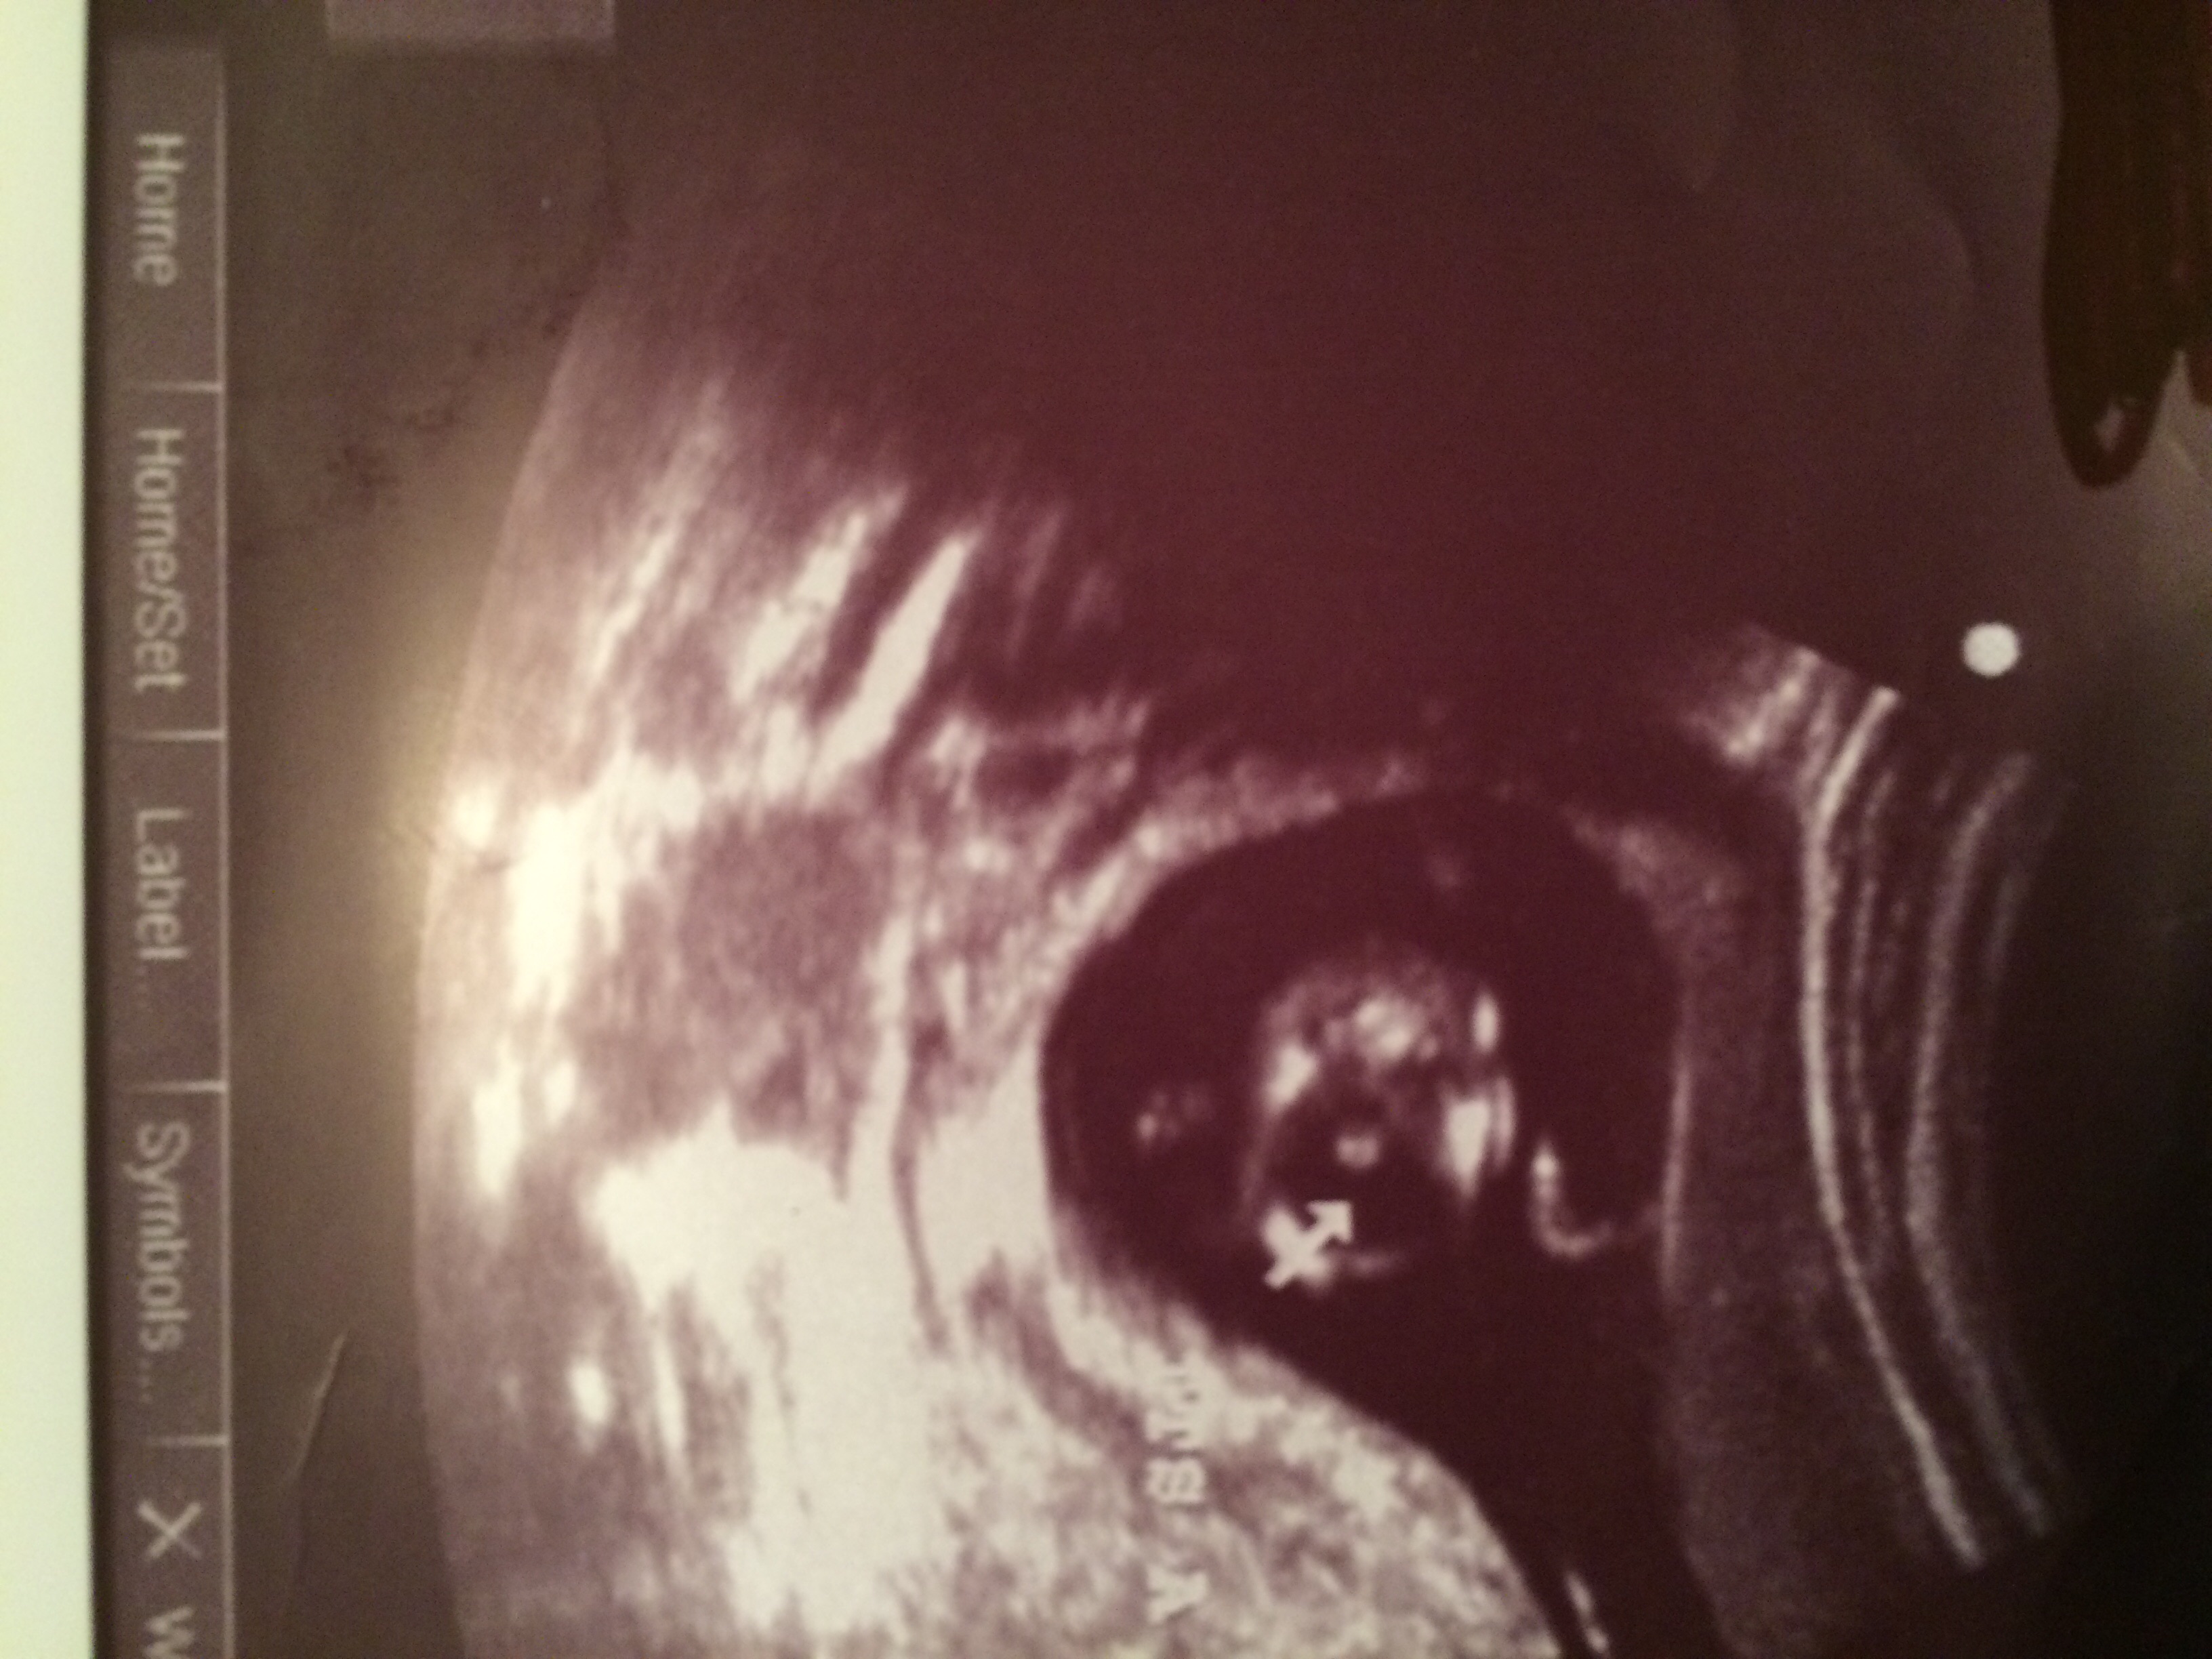

Attachment 28450Attachment 28451

I do not have any profile/nub shots.

Id say Boy!

I'd say a very proud young man.

Definitely looks like a boy to me! :) :superhero:

I would say boy!

Looks like a boy to me!

Yup boy to me too

Confirmed BOY!!!